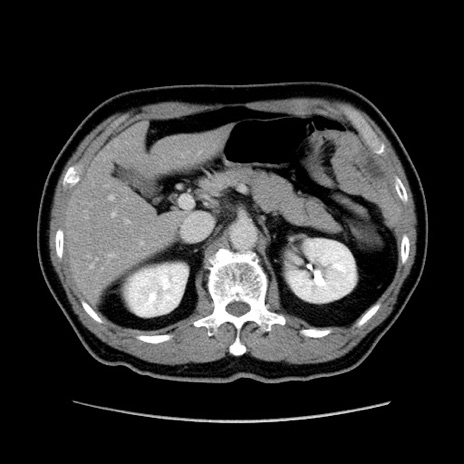

症例34(横断像)

【症例】60歳代 男性

【主訴】右鼠径部膨隆

【現病歴】1年程前より右鼠径部膨隆あり。自己にて還納可能だったため放置していた。3時間前より右鼠径部の脱出を認め、還納困難となり受診。

【身体所見】右鼠径部に小児頭大の膨隆あり。弾性硬であり、用手還納は困難。左鼠径部にも膨隆を認める。脱出はなし。